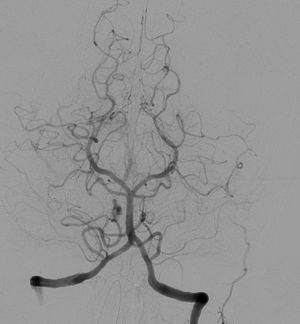

Angiography